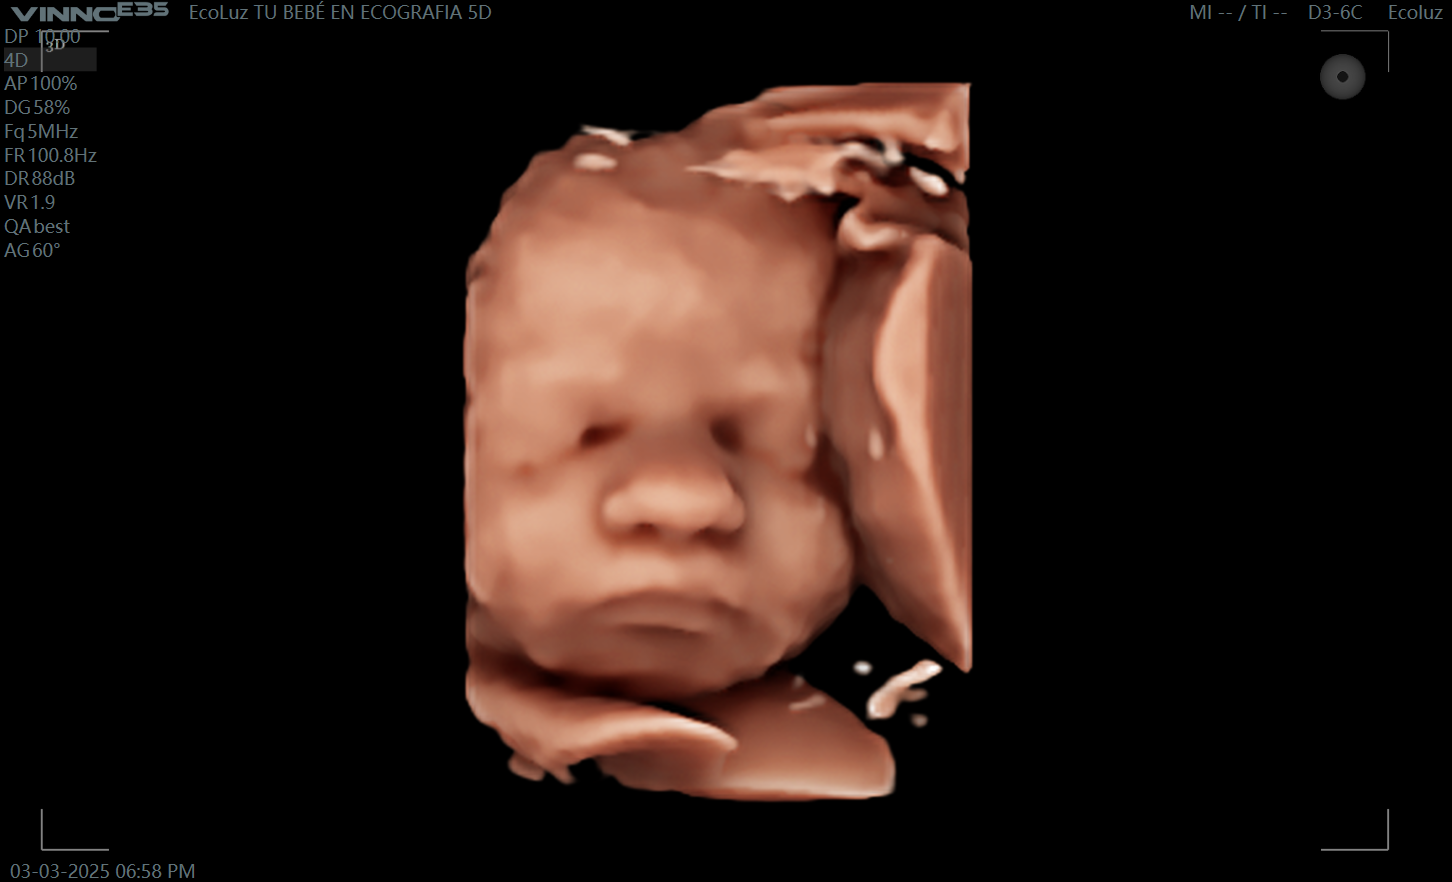

A las 30 semanas, tu bebé ya tiene una apariencia muy similar a la que tendrá al nacer. La eco 30 semanas permite disfrutar de imágenes claras, emotivas y llenas…

En esta etapa del embarazo, la eco 30 semanas muestra un bebé más grande y con menos espacio para moverse, lo que facilita ver su rostro más fijo en pantalla.…

Muchas familias consideran la ecografía de 30 semanas como una de las más impactantes visualmente. La definición del rostro y los detalles son sorprendentes. 💫 En EcoLuz 5D creamos un…

A las 30 semanas, el bebé ya tiene una expresión muy reconocible. La ecografía 30 semanas permite captar gestos únicos que emocionan a toda la familia.

Sí, la eco de 30 semanas suele ofrecer imágenes muy definidas gracias al desarrollo avanzado del bebé. Sus rasgos están prácticamente formados y la experiencia es muy emocionante. En EcoLuz…